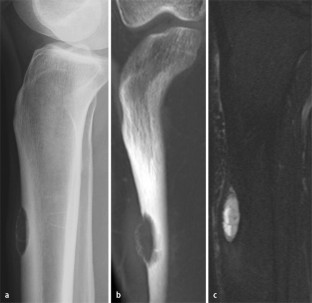

Abb. 4